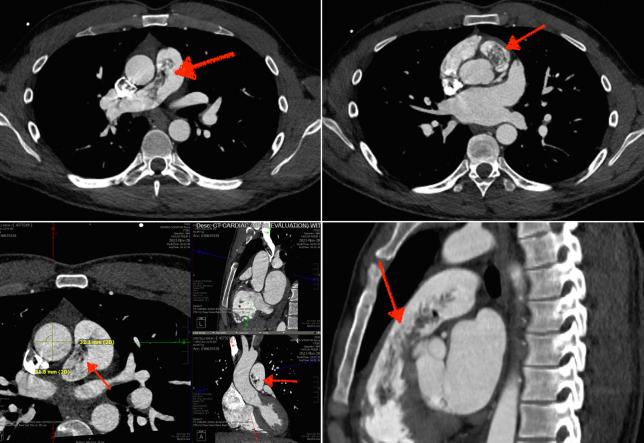

This case report describes the management of a 30-year-old male patient with a history of an advanced nonseminomatous germ cell tumor, hip fracture complicated by extensive deep vein thrombosis and pulmonary embolism, and on apixaban presenting with asymptomatic intracardiac teratoma and abdominopelvic metastases. Multidisciplinary intervention, including successful surgical excision of the intracardiac mass, highlights the importance of coordinated care and vigilant follow-up in optimizing patient outcomes and preventing life-threatening complications.

本病例报告描述了一名30岁男性患者的治疗情况,该患者有晚期非精原细胞瘤性生殖细胞肿瘤病史,髋部骨折并发广泛深静脉血栓形成和肺栓塞,正在服用阿哌沙班,现出现无症状心脏畸胎瘤和腹盆腔转移。多学科干预,包括成功手术切除心脏肿块,凸显了协调护理和密切随访在优化患者预后及预防危及生命并发症方面的重要性。